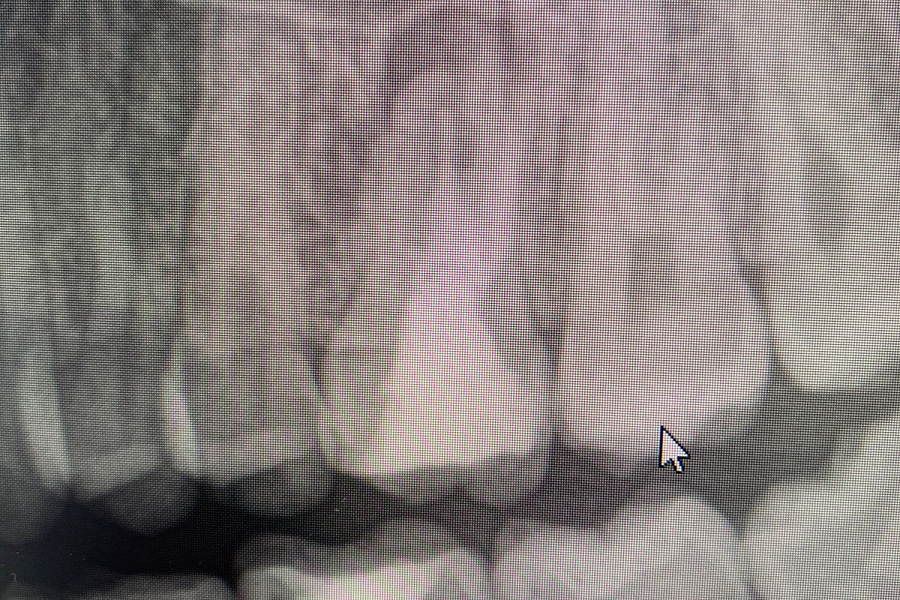

Через 6 месяцев после подсадки кости - контрольный снимок и установка зубного имплантата.

Спустя 6 месяцев пациент готов к протезированию.

Результат лечения